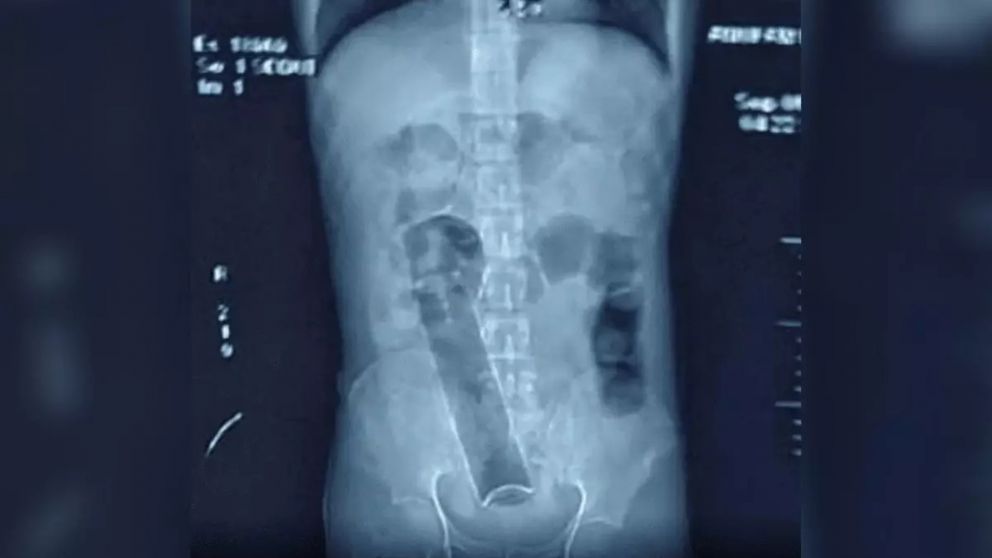

Allí, los médicos realizaron varias radiografías, que revelaron que tenía, por motivos que no trascendieron, una lata de desodorante de unos 20 centímetros inexplicablemente alojada en el colon, cerca del ano.

Según revelaron los informes, la lata estuvo dentro de su cuerpo durante 20 días, durante los cuales el hombre no pudo hacer sus necesidades. Los médicos creen que la vida del joven podría haber estado en peligro si no se hubiera presentado en el hospital.